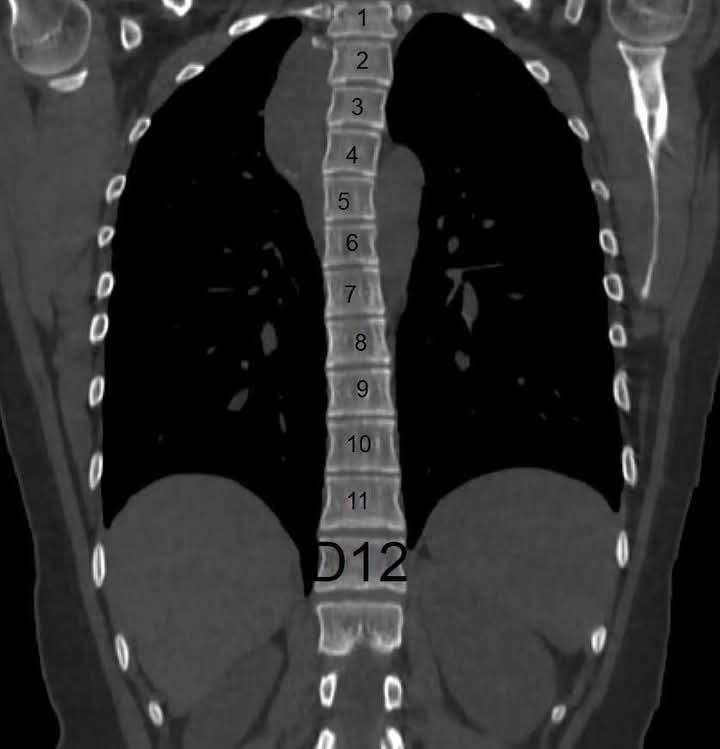

نجح فريق طبي بقسم جراحة المخ والأعصاب والعمود الفقري وقسم جراحة القلب والصدر بمستشفيات جامعة أسيوط، في إجراء عملية جراحية دقيقة لطالبة بكلية التربية الرياضية تبلغ من العمر ٢٠ عاما، تعاني من وجود ورم بالنصف الصدري ممتد للعمود الفقري.

كانت مستشفيات جامعة أسيوط قد استقبلت فتاة تعاني من كحة مزمنة مصحوبة بغثيان وآلام بالصدر وبمناظرة الحالة بالإشاعات والفحص الإكلينيكي تبين وجود ورم بالصدر ممتد عبر القناة العصبية للحبل الشوكي، ليقوم الفريق الطبي  بإجراء عملية نوعية مشتركة استغرقت ٤ ساعات  وتم خلالها استخدام أحدث التقنيات الجراحية "منظار الصدر الجراحي و الميكروسكوب الجراحي"،  لاستئصال الورم بالكامل من حول الحبل الشوكي ومن داخل الصدر عن طريق فتحة صغيرة جانبية بالصدر وفتحة صغيرة بالظهر.